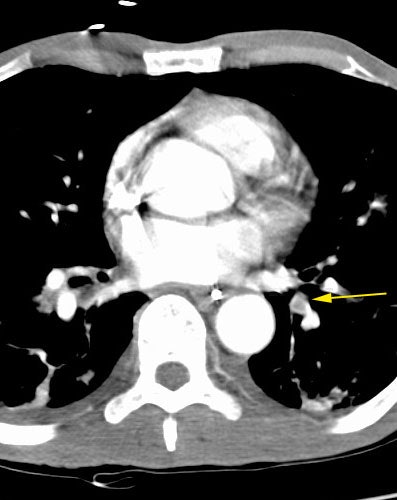

Mucous plug mimicks PE

The examination demonstrated an apparent pulmonary embolism to the left lower lobe (yellow arrow). However, when the images are viewed in a cine format, the abnormality can be seen to clearly represent a mucous filled bronchus. Cine display of the images is crucial to proper CT PE exam interpretation.

Click image to view cine (1 MB)